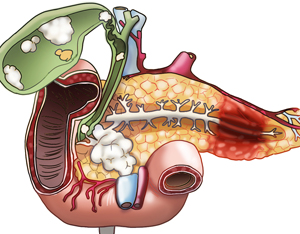

췌장은 해부학적으로 두부(머리 부분), 체부(몸통 부분), 미부(꼬리 부분)로 나눠집니다. 두부는 담관(담즙의 배출 통로)과 연결되어 있어 두부에 췌장암이 발생하면 담관이 막히면서 황달이 일어날수 있어요.

미부는 비장과 연결되어 있죠. 소장과 대장 일부에 혈액을 주는 상장간막 동맥은 대동맥으로부터 분지 되어 췌장과 인접해 주행하죠. 췌장에 일어나는 종양은 인슐린 등 호르몬을 분비하는 내분비 세포에서 출현하는 종양(5~10%)과 소화 효소의 분비와 맺어진 외분비 세포에서 소망하는 종양(90% 이상)으로 나눌 수 있죠.

췌장은 위장의 뒤쪽 몸통의 중앙에 붙어있고 있었고 위, 십이 지장, 소장, 대장 등의 장기에 둘러싸여 있어서 췌장암을 초기 발견하는게 정말 쉽지 않습니다 췌장암의 90% 이상은 췌관의 외분비 세포에 암이 전파되어 선암으로 예사로 췌장암입니다.

황달은 췌장머리췌장 머리 부분에 위치하고 있는 종양이 총담관에서 소장으로 계속되는 부분을 폐쇄하여 담즙의 흐름을 억제해 혈액 내 빌리루빈 수치가 상승해서 생기는 것으로, 췌장 머리 부분에서 일어나는 암의 약 80%에 있죠. 몸통이나 꼬리에 종양이 생성한 경우에는 5~6% 정도만 황달이 나타나는데, 거의 황달이 생겨날 때는 이미 암세포가 췌장 전체에 퍼져 간이나 림프절로 전이될 정도로 병이 진전된 상태가 많답니다. 혈액 내 빌리루빈 수치의 상승으로 황달이 나타난 경우에는 피부와 눈의 흰자위가 노란색으로 변하고, 소변 색이 갈색으로 되며 피부의 가려움증이 유발되요.